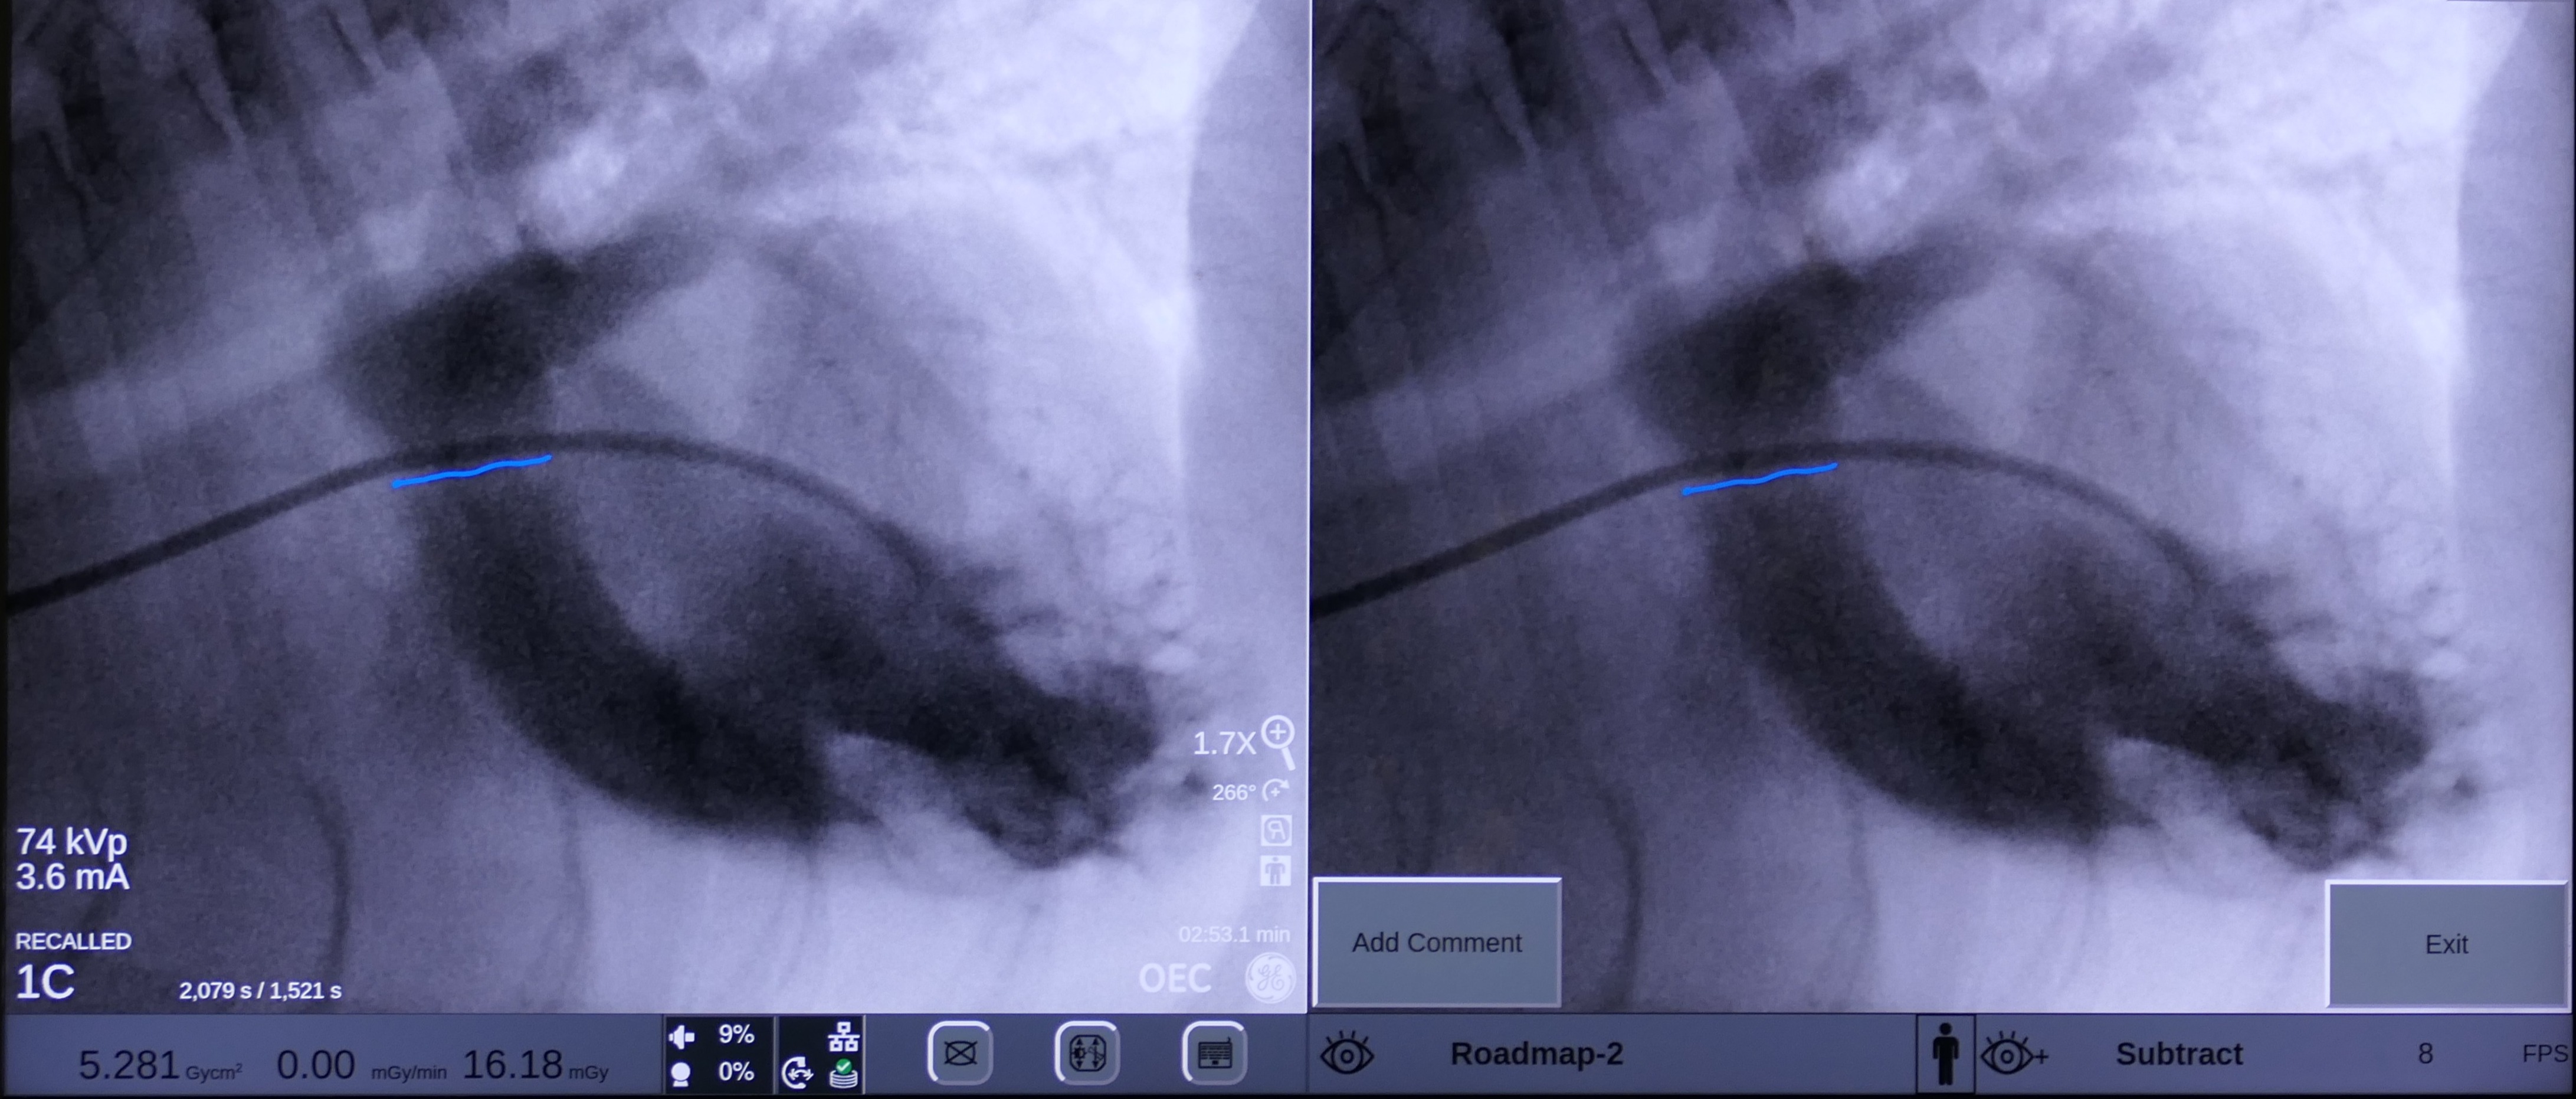

On May 7 2024, Snoop underwent a balloon valvuloplasty at MVRH. The procedure involved placing Snoop under general anesthesia and accessing the affected valve via the external right jugular vein. In order to gain access to the heart, a vascular introducer is first placed into the vein. This allows exchanging various wires and catheters without causing blood loss. Then, using fluoroscopy (Live X-rays) a catheter is advanced into the heart. This catheter has a small air balloon in its tip working as a “sail” and flowing downstream into the heart. Once the anatomy is assessed by using contrast, a Guire is placed to be used as a roadmap. Over this wire, a catheter with a large balloon in its tip is positioned across the fused valves. Once the balloon is inflated, the high pressures reached with this balloon separate the valve leaflets, decreasing the obstruction. This balloon reaches up to 18 atmospheres of pressure, and to put this in perspective, it is the equivalent of roughly stretching it with 260 pounds of force.